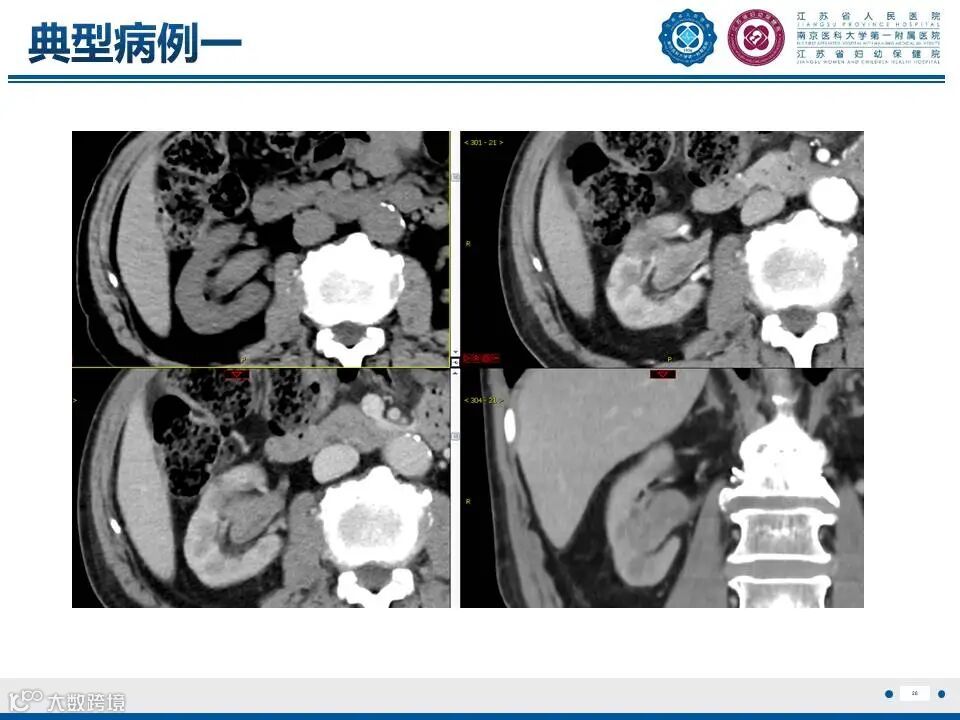

肾实质肾盂尿路上皮癌——水泄不通 II

肾实质肾盂尿路上皮癌——水泄不通 II 鼎湖影像